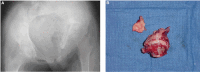

Musculoskeletal tuberculosis (TB) accounts for approximately 10% of all extrapulmonary TB cases in the United States and is the third most common site of extrapulmonary TB after pleural and lymphatic disease. Vertebral involvement (tuberculous spondylitis, or Pott's disease) is the most common type of skeletal TB, accounting for about half of all cases of musculoskeletal TB. The presentation of musculoskeletal TB may be insidious over a long period and the diagnosis may be elusive and delayed, as TB may not be the initial consideration in the differential diagnosis. Concomitant pulmonary involvement may not be present, thus confusing the diagnosis even further. Early diagnosis of bone and joint disease is important to minimize the risk of deformity and enhance outcome. The introduction of newer imaging modalities, including MRI (imaging procedure of choice) and CT, has enhanced the diagnostic evaluation of patients with musculoskeletal TB and for directed biopsies of affected areas of the musculoskeletal system. Obtaining appropriate specimens for culture and other diagnostic tests is essential to establish a definitive diagnosis and recover M. tuberculosis for susceptibility testing. A total of 6 to 9 months of a rifampin-based regimen, like treatment of pulmonary TB, is recommended for the treatment of drug susceptible musculoskeletal disease. Randomized trials of tuberculous spondylitis have demonstrated that such regimens are efficacious. These data and those from the treatment of pulmonary TB have been extrapolated to form the basis of treatment regimen recommendations for other forms of musculoskeletal TB.